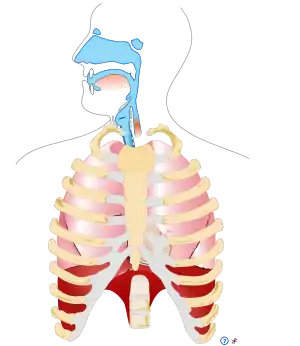

Respiratory cryptosporidiosis

Symptoms of upper respiratory cryptosporidiosis include:

- Inflammation of the nasal mucosa, sinuses, larynx, or trachea[2]

- Nasal discharge[2]

- Voice change[2] (e.g., hoarseness)[8]

Symptoms of lower respiratory cryptosporidiosis include: